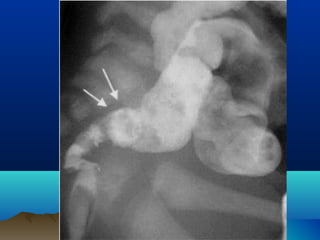

3-BARIUM ENEMA

• Types of enemas

 Pneumatic (air enema)

 Hydrostatic (fluid enema)

 Barium Enema (fluid with contrast)

Barium Enema: